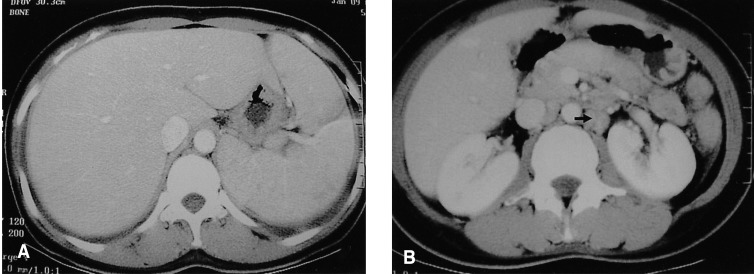

Figure 2

Abdominal CT. (A) Demonstrated diffuse hepatosplenomegaly. (B) Demonstrated left paraaortic lymphadenopathy (arrow).